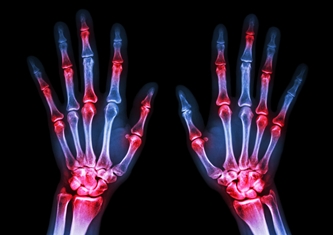

Кости, лишенные амортизатора, начинают тереться друг о друга. Организм пытается защитить себя: чтобы увеличить площадь соприкосновения и снизить нагрузку, он начинает наращивать костную ткань по краям суставных площадок. Эти наросты называются остеофитами. Именно их мы и видим как твердые, неподвижные узелки на пальцах.

В медицине их разделяют по локализации:

- Узелки Гебердена. Появляются на тыльной или боковой поверхности дистальных фаланг пальцев (то есть самых дальних суставчиков, которые находятся прямо перед ногтем). Чаще всего страдают указательный и средний пальцы, а также мизинец. У женщин они встречаются примерно в 10 раз чаще, чем у мужчин, что говорит о связи с гормональными изменениями, особенно в период менопаузы.

- Узелки Бушара. Располагаются в области средних суставов пальцев (проксимальных межфаланговых). Они часто развиваются на фоне уже имеющихся узелков Гебердена и делают пальцы truly узловатыми, веретенообразными.

Рентгенографию кистей. На снимке видно сужение суставной щели, остеофиты (те самые шипы).